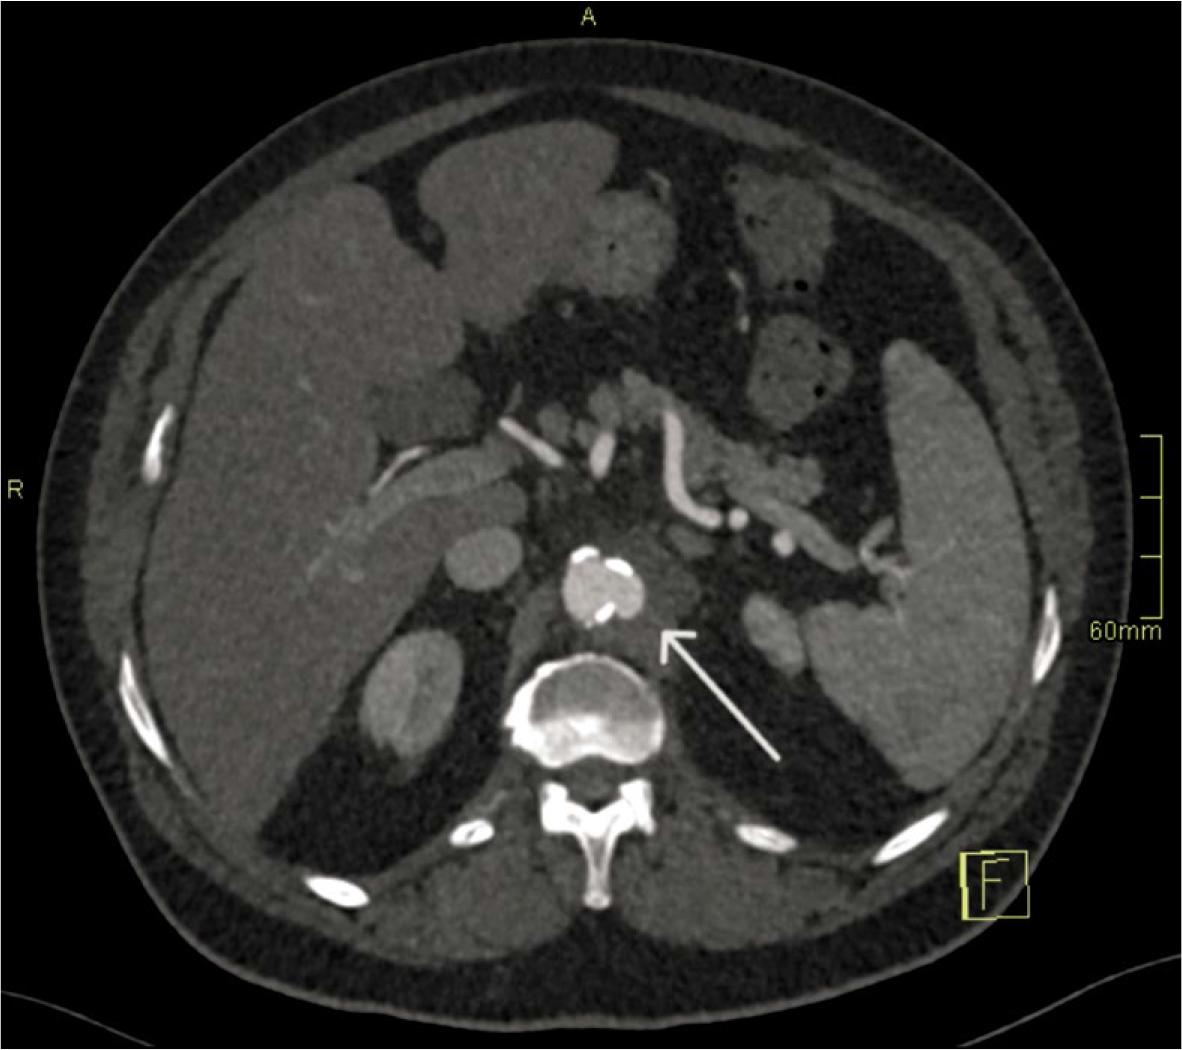

FIGURE 2.